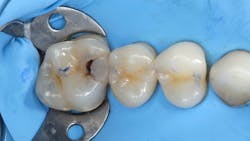

In addition to optimal bonding, the rubber dam may retract the tissues when placed properly, improving our visualization of finish lines, margins, and adhesive materials. One of dentistry’s rubber dam advocates, Dr. Hunter Brinker (the inventor of the B1-B6 clamps), often said “to see is to know” when referring to the benefits of the rubber dam to improve attention to detail through better visual access. It is interesting to note that when the rubber dam is properly placed, it will not only retract the tongue, lips, and cheeks, but it will also atraumatically retract the gingiva, typically 2–3 mm, and expose areas that could not be visualized by any other nonsurgical means (figures 3–5).

After removing a two-week-old provisional, it’s a rare day that we don’t experience some minor inflammation of the soft tissues. Even with the best prototypes/provisionals and meticulous oral hygiene, gingival tissues will bleed, exude fluids, and generally cause problems when isolating teeth for adhesive delivery. With a direct composite, the existing decay is an irritant, and the best isolation device will not address the bleeding tissue adjacent to an extensive class II cavity.

With an inverted rubber dam, however, bleeding becomes a nonissue and allows the clinician to focus on preparation design, pulpal protection, adhesive strategies, and restoration placement—all in a clean and well-sealed environment.3 “Beating the blood” need not be your approach when one of dentistry’s least-used gems is close at hand (figures 6 and 7).